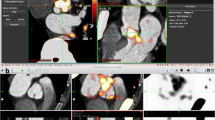

Intense aortic valve 18F-fluoride uptake was observed in all seven patients with aortic stenosis on both PET/CT and PET/MR (Figure 2). Moreover, the pattern of tracer uptake with the valve was similar across the two modalities, localizing predominantly to the tips of the valve leaflets and the commissures (Figure 2).

18F-Fluoride uptake in a patient with moderate aortic stenosis. The columns represent the imaging modality and rows the corresponding view. (A, F, G) Calcification of the aortic valve (non-coronary cusp predominantly, yellow arrows). (B, G, L) The coronary magnetic resonance angiogram in the same views. Calcification cannot be appreciated on MR but the raphe between the non-coronary cusp and left coronary cusp appears thickened (B). PET/CT shows uptake overlaying these areas of calcification (C, H, M). Note the uptake also over the calcified mitral annulus (M, red arrow) and arterial wall of the descending aorta (M, red arrow). Radial GRE-fused PET/MR shows 18F-fluoride uptake in the same areas as the PET/CT (D, I, N). (E, J, O) The corresponding views in the Dixon PET/MR attenuation correction map. Again 18F-Fluoride follows a similar pattern to PET/CT but note the image artifact in (O) (white arrow)

Visual agreement in determining coronary 18F-fluoride uptake on PET/CT and PET/MR was generally good in non-stented regions. Across the total population, a total of 28 (1.56 plaques/patient) non-stented coronary plaques demonstrated increased 18F-fluoride uptake on PET/CT. PET/MR identified excellent agreement with increased uptake in 28 (97%) of these lesions irrespective of the method of attenuation correction (κ 0.93, CI 0.837 to 1.000). Four plaques demonstrated increased 18F-fluoride uptake on the PET/MR scans but not on PET/CT.

In the native coronary arteries, SUVMAX values were lower on PET/MR (using both attenuation correction techniques) than on PET/CT consistent with findings in the valve. TBRMAX values were comparable, although slightly higher using GRE PET/MR than PET/CT (bias − 11%, limits of agreement − 54% to 32%; Table 3; Figure 4B, 5).

Influence of stents on coronary artery 18F-fluoride uptake. Each row represents a patient and the columns the imaging modality. Patient 1: Axial view of complex calcified plaque in the proximal left anterior descending artery (pLAD) (yellow arrow, A) on CCTA. The corresponding CMRA can be appreciated in (B). PET/CT (C) shows focal uptake overlying the complex plaque in the pLAD (yellow arrow) and uptake in the medial wall of the aorta. Both the radial GRE (D) and Dixon PET/MR (E) demonstrate focal uptake within the LAD plaque (yellow arrows) as the PET/CT. However, note the absence of uptake within the aorta demonstrating the utility of later imaging in improving signal-to-noise ratios. Also note airway artifact behind the behind the left atrium and superior vena cava (red arrows) with the Dixon PET/MR (E). Patient 2: Anterior myocardial infarction with primary PCI to the LAD. (F) The 2-chamber view of the metallic stent on the CCTA (yellow arrow). (G) The corresponding CMRA. Focal 18F-fluoride uptake can be appreciated on the PET/CT within the body of the stent (H, yellow arrow). (I) The radial GRE PET/MR affected by severe PET dropout over the whole stent despite marked amplification of the blood pool. Employing the Dixon AC map sees the culprit artery signal within the LAD stent return (J, yellow arrow). Patient 3: Modified short-axis CCTA with stent in the proximal RCA (yellow arrow). (L) The corresponding CMRA image of the stent (yellow arrow). (M) Focal 18F-fluoride uptake over the body of the stent (yellow arrow) on PET/CT. Radial GRE PET/MR shows PET dropout over the body of the stent (N, yellow arrow). Similarly, Dixon PET/MR is affected by the same artifact precluding assessment of PET activity within the stent (O, yellow arrow). Patient 4: Short-axis CCTA (P) shows a diseased right coronary artery (RCA) and a stent placed in the pLAD (yellow arrow) after primary PCI. Corresponding CMRA can be appreciated in (Q). Uptake within the proximal to mid RCA (red arrow) and culprit LAD (yellow arrow) can be appreciated on the PET/CT (R). PET/MR also shows focal 18F-fluoride uptake in the mid RCA with radial GRE PET/MR (S, red arrow) but note the absence of LAD uptake in the region of the stent (yellow arrow). On Dixon PET/MR (T), the LAD uptake is visible (yellow arrow) alongside focal RCA uptake (red arrow)

Coronary stents caused severe artifact on both the radial GRE and Dixon MR attenuation correction maps, resulting in marked dropout of the PET signal and precluding accurate analysis. Agreement between PET/CT and PET/MR in determining 18F-fluoride uptake within coronary stents was therefore poor (Table 3). Increased 18F-fluoride uptake was observed on PET/CT in 18 coronary stent segments. On radial GRE PET/MR, 18F-fluoride uptake in the body of the stent was obscured by artifact in all 18 stents, although increased uptake could be appreciated either at the proximal or distal end of the stent in 6 cases. Artifact was also observed with Dixon PET/MR, although it was less pronounced than the radial GRE PET/MR (Figure 4O), with increased 18F-fluoride activity observed at the margins of the stent in 7 cases (Suppl. Figure 3). Interestingly this artifact was not present in heavily calcified arteries or valves on either PET/MR AC map. The differences in tissue classification between both PET/MR attenuation maps can be further appreciated in Supplementary Figure 1.

Unfortunately, coronary PET/MR is greatly hampered by artifact at the site of intra-coronary stent implantation. This is due to magnetic field inhomogeneities and subsequent MR signal loss affecting attenuation correction of the PET data (Suppl. Figure 1). It was particularly prevalent with radial GRE PET/MR, where substantial ‘halo’ like PET dropout occurred at the site of all stents imaged (Figure 4I+N and Suppl. Figure 3B). Although less dramatic with the Dixon PET/MR scans, the degree of artifact was such that reliable interpretation of PET signal remained impossible (Suppl. Figure 3C). Attempts to overcome this limitation using novel MR gap-filling algorithms have shown early promise.19 Interestingly, areas of dense coronary and valvular calcification were not affected by PET dropout.